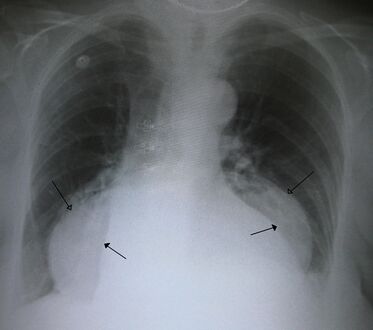

فتق حجابي كبير في صورة للصدر بالأشعة السينية، حيث يُميز بأسهم مفتوحة على النقيض من حدود القلب التي تتميز بأسهم مغلقة.